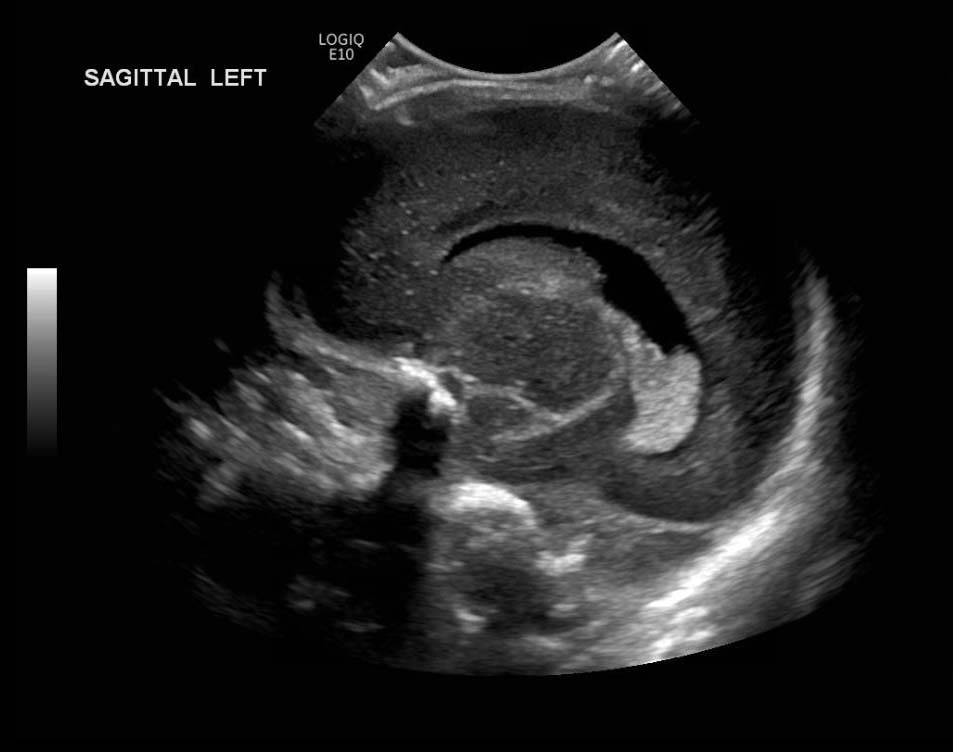

Age: 4 days (born at 24 weeks)

Sex: Male

Indication: Evaluate for germinal matrix hemorrhage

Grade 2 germinal matrix hemorrhage

Sample ReportLeft germinal matrix hemorrhage involving the caudothalamic groove and layering in the occipital horn of the left lateral ventricle without hydrocephalus (grade 2).

No abnormal brain parenchymal echogenicity or extra-axial collections.

Premature sulcation pattern.